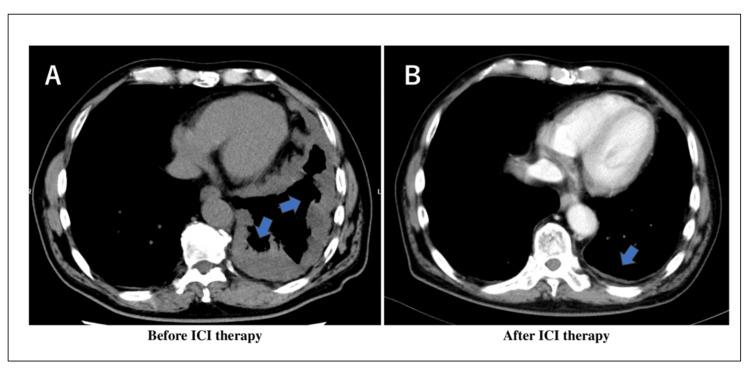

免疫检查点抑制剂(ICI)疗法通过激活免疫系统,代表了癌症治疗的重大进展。然而,由于免疫失调(ITI-DI),ICI会引发矛盾的免疫疗法相关感染。在此,我们报告了一名接受ICI治疗的恶性胸膜间皮瘤患者发生水痘-带状疱疹病毒(VZV)脑膜炎,其特征为意识障碍和脑脊液异常。尽管使用阿昔洛韦进行抗病毒治疗有效地将VZV DNA降低到检测不到的水平,但仍观察到持续性脑脊液单核细胞增多,这类似于免疫重建炎症综合征(IRIS)。该病例突出了ICI治疗期间复杂的免疫相互作用,即免疫激活通过不同于经典免疫抑制的机制,反常地导致对某些感染的易感性。我们的研究结果强调了将IRIS和ITI-DI识别为需要特定临床考虑的不同实体的重要性。我们建议,对非典型感染进行全面监测并实施针对病原体的管理策略,是接受ICI治疗患者护理的重要组成部分,特别是考虑到这些治疗所创造的独特免疫环境。